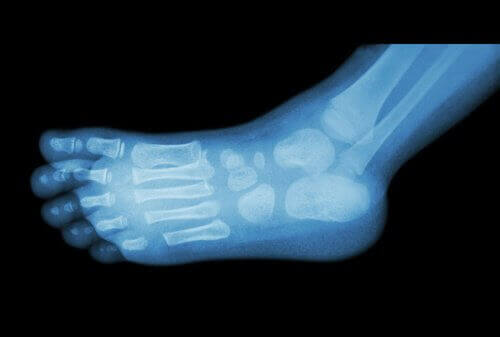

Lääkärit käyttävät röntgeniä luupiikin diagnosoimiseen.

Luupiikin tunnistaa kuitenkin yleensä ensi näkemältä, sillä ne ovat pieniä ulokkeita, jotka syntyvät kalkin kerääntymisestä kantapäähän.